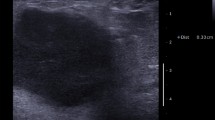

Forty-two women of the 520 died of breast cancer (8%) while 53 women had non-breast cancer deaths (10%) during the follow-up period. Kaplan–Meier survival curves for three equal size groups based on stiffness are shown in Fig. 1 and curves by US size in Fig. 2. Kaplan–Meier survival curves according to core biopsy grade are shown in Fig. 3.

All US scans were performed by one of five breast radiologists or an advanced radiography practitioner trained to perform and interpret breast ultrasound. These practitioners had between 7 and 22 years of breast ultrasound experience and had at least 12 months of experience performing SWE of solid breast lesions. Four SWE images in two orthogonal planes were obtained. The region of interest (ROI) utilized in all cases was 2 mm in diameter. Mean stiffness in kPa was taken as the average of the values taken from four SWE images taken in two orthogonal planes. The maximum US diameter used in the analysis was the largest obtained in any of the three planes. All scans were performed using an Aixplorer® ultrasound system (SuperSonic Imagine, Aix en Provence, France). Institutional Review Board ethical approval was waived for this retrospective analysis of prospectively recorded data and all patients gave permission for evaluation of their images.